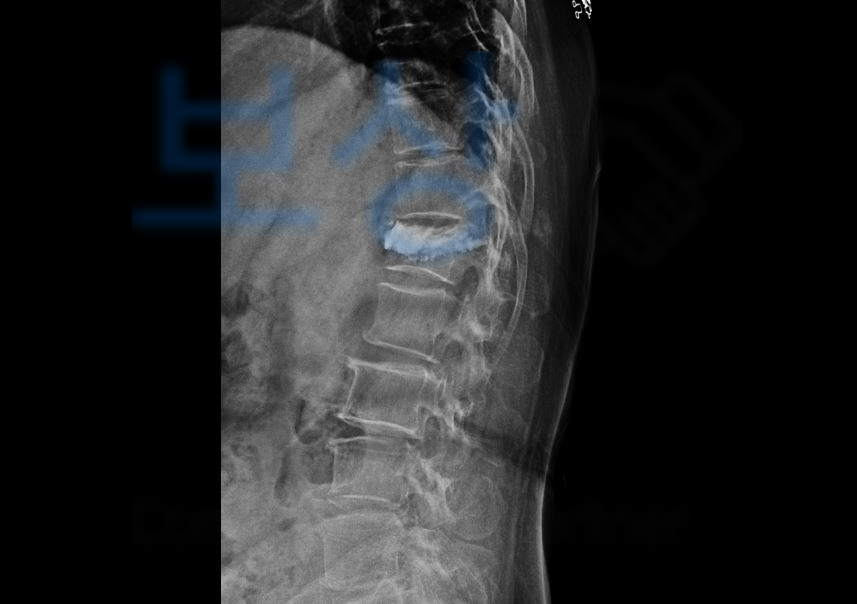

하지만 윤@@님은 골절의 정도가 심해 진단서에 쓰여있는 경피적 척추성형술골시멘트술을 받게 되셨는데요,

여기서 경피적 척추성형술과 골시멘트술은 동일한 시술로 목표물에 의료용 시멘트를 주사해 척추의 안정성을 향상시키는 목적이 있습니다. 윤@@님은 지인이 후유장해보험금을 알아보라는 권유에 보상파트너로 연락주셨습니다.

그 결과 고객님은 무려 지급률 50%에 해당하셨고 저희는 **보험사에 손해사정서를 송부하여 ** 보험금 청구를 진행하였습니다.

물론 그 과정에서 기존의 각도를 측정하는 등 보험사와 약 한달간의 분쟁이 오갔지만 지급률 50% 모두 인정받아